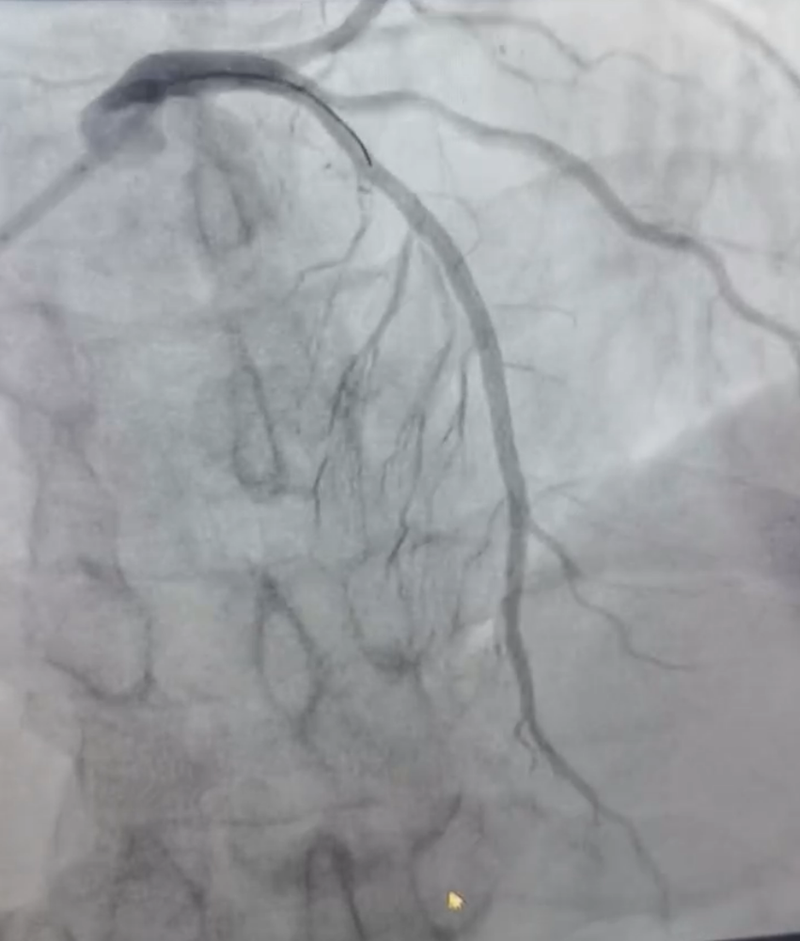

2:支架植入后狹窄完全解除,血流通暢